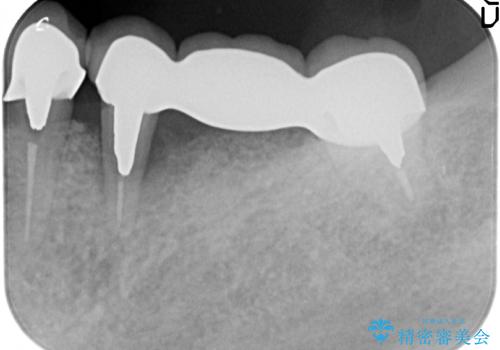

X線写真より、過度な咬合支持負担により支台となる歯の周囲の骨吸収が認められます。今後安定してしっかりとかめるような環境を整備するためにインプラント治療を選択しました。

ブリッジ治療は支台となる歯が弱いと、今回のように周囲の骨が吸収したり歯が割れてしまったりといったトラブルがおきます。咬合力に対抗するため、今回はインプラントを用いて機能回復を行いました。